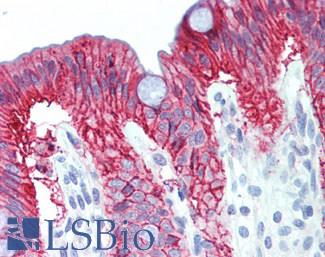

CK20 (KRT20)

Anti-KRT20 / Cytokeratin 20 antibody IHC staining of human small intestine. Immunohistochemistry of formalin-fixed, paraffin-embedded tissue after heat-induced antigen retrieval. Antibody LS-B10488 dilution 1:200.